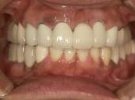

40代女性

奥歯が欠落して、全く噛めないと大変お困りの状態でした。

治療に1年半程要しましたが、熱心に通院してくださいました。

魚介類・お肉なんでも噛めるようになり、今ではニコッと笑える日々で楽しいですと、

アンケートにも答えてくださいました。

| 治療前 | ||

| 治療後 | ||